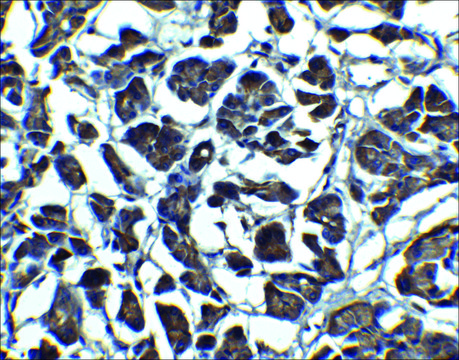

immunocytochemistry: suitable